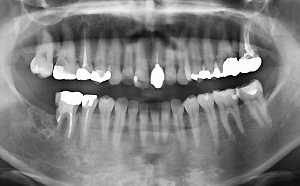

図❶ 初診時のパノラマX線写真

画像所見:パノラマX線写真では、欠損した7部骨内に、多房性、泡沫状の透過像を認め、6の遠心根は吸収していた(図❶)。CT画像では同部に細かい泡沫状の隔壁を有しており、内部に石灰化像はなかった。境界は比較的明瞭で、周囲への浸潤は認めなかった。また、下歯槽神経には近接していなかった(図❷)。